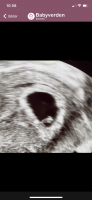

Hva tror dere ? Innvendig ultralyd

Her er ultralydene i uke 6 og 8 uenige

Uke 6 ser det ut som morkaka er mest mot venstre side og uke 8 er den på høyre side. Begge er tatt innvendig, men forskjellig ul apparat

Kort fortalt er det gjort en stor studie på 5000 tidlig ultralyder om at jentefoster fester seg på venstre side (morkake på venstre side) og omvendt for guttefoster (når man tar vaginal ultralyd.. om man tar utvendig ultralyd er sidene byttet om såklart) skal visst være 97 % sikkert. Prøv å Google det![]()